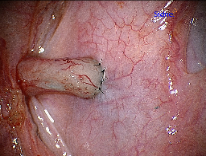

Epididymovasostomy

Epididymovasostomy is required during vasectomy reversal when there is absent sperm in the vas deferens. This signifies that a secondary epididymal obstruction has developed upstream from the vasectomy site. This situation is encountered in approximately 40% of individuals after a vasectomy. Epididymovasostomy can only be performed using a high powered operating microscope, under general anesthesia, by microsurgeons using the finest suture (10-0 nylon).